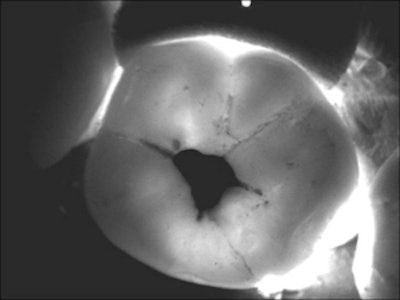

The DIFOTI system uses visible light to illuminate cracks and early caries.

One of the first optical devices developed specifically for caries detection was the DIFOTI (digital imaging fiber-optic transillumination) system, developed and marketed by Electro-Optical Sciences. Introduced in 2001, it is the only instrument of its kind to be approved by the FDA for the detection of incipient, frank, and recurrent caries. A single fiber-optic cable in the patented mouthpiece delivers visible light to a tooth's smooth surfaces. As the light travels through layers of enamel and dentin, it scatters in all directions toward the nonilluminated surfaces. The light is then directed through the mouthpiece to a CCD camera in the handpiece. The camera digitally images the light emerging from the various surfaces of the teeth. These images are displayed on a computer monitor in real-time and stored on the hard drive.

A number of clinical studies involving DIFOTI have been conducted over the years, and the findings consistently support the viability of this device for imaging cracks and detecting some early caries. For example, a 2005 study that looked at the DIFOTI system for evaluating early approximal lesions concluded that although the device was not able to measure the depth of a lesion in any of the samples, it was able to show surface changes associated with early demineralization as early as two weeks (Journal of the American Dental Association, December 2005, Vol. 136:12, pp. 1682-1687).